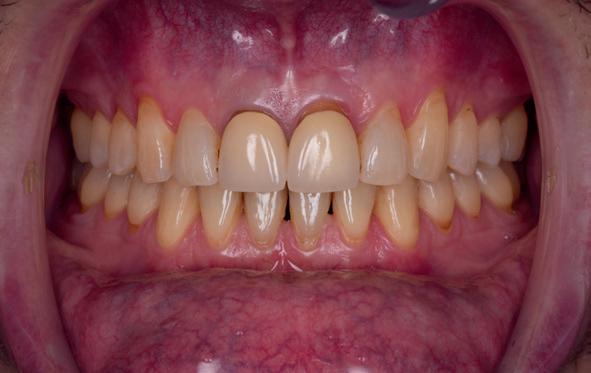

Esthetiek in de tandheelkunde, met name in het front, is een samenspel tussen de roze zachte weefsels en de witte harde weefsels. In het Engels wordt dit ook wel aangeduid met “pink and white esthetics”, waarbij het verkrijgen van correcte pink esthetics over het algemeen een grotere uitdaging vormt dan de white esthetics. Deze roze esthetiek is vooral van belang bij gebitselementen waarbij sprake is van recessie (het terugtrekken van de gingivalijn, waardoor de radix en een langere tand zichtbaar worden). De situatie wordt nog uitdagender wanneer een tand of kies niet is aangelegd, of in het verleden is verwijderd. Het element zorgt er immers voor dat de gingiva rondom de natuurlijke kroon ligt en dat er voldoende weefseldikte rondom deze kroon aanwezig is. Als het element ontbreekt, groeit het alveolaire bot dicht, omdat er geen radix meer is, en daarmee ook de mucosa (wanneer er geen element meer aanwezig is, spreken we niet meer van gingiva maar van mucosa), die dan afgevlakt is. De papillen tussen de afwezige elementen vlakken dan ook af.

Om één of meer afwezige elementen te herstellen bij een vaste voorziening, kan er een etsbrug of kunnen er implantaten worden geplaatst. De esthetiek valt of staat hierbij met de aanvulling van de zachte weefsels, zowel in de vorm van verbreding hiervan als het creëren van een zogenoemd emergence profile –dat wil zeggen dat de tand op een natuurlijk ogende wijze vanuit het tandvlees tevoorschijn moet komen.

Op 16-jarige leeftijd werd de patiënt door haar behandelend orthodontist naar de auteur verwezen voor een restauratieve oplossing voor de afwezige 11 en 21. In de tussenliggende periode had patiënt een retainer gedragen met twee kunststof tanden (afbeelding 1). Zowel de patiënt als haar moeder hadden een sterke voorkeur voor een implantaat gedragen vaste oplossing. Gezien haar jonge leeftijd was dit echter nog geen optie, omdat er nog verticale groei te verwachten viel. Implanteren op jonge leeftijd – dat wil zeggen vóór het 21e levensjaar – kan resulteren in een infrapositie van het implantaat, omdat de rest van het gebit nog verticaal kan doorgroeien.

Middels shared decision making werd het volgende plan overeengekomen: eerst zou er een etsbrug met vleugels op de 12 en 22 worden vervaardigd, om op 21-jarige leeftijd verder te gaan met implantologie.

van de patiënt, om eerst weer vaste apparatuur terug te plaatsen om de radices in een divergerende stand te plaatsen. Gelukkig verliep deze behandeling voorspoedig. (afbeelding 2 -4). Het volgende behandelplan werd gemaakt:

• Aanvulling zachte weefsels met de VISTA techniek en een vrij gingivatransplantaat uit het palatum links en direct dragen van de essix retainer

Na 4 weken intra-orale scan voor de etsbrug en kleurbepaling bij de technicus

• Plaatsen van de etsbrug met een composietcement

Voordat er gescand kon worden voor een etsbrug, werd een studiemodel vervaardigd om met de technicus te overleggen of er voldoende ruimte was voor 2 centrale incisieven in de mesio-distale zin en of er voldoende ruimte was in occlusie voor de vleugels van de etsbrug. Er hoeft enkel nog aan de 12 en 22 pala-

tinaal geslepen te worden als er geen 1,5 mm ruimte voor de vleugels behaald kan worden. De ruimte was op de dunste plekken 1 mm, dus een kleine preparatie in de 12 en 22 palatinaal was nodig. Omdat de kaak volledig afgevlakt was en dun was geworden, kunnen de dummies van de etsbrug enkel op de kaak “gelegd worden”, maar daarbij zijn er geen papillen en staat de cervicale rand van de dummies net voor de kaak. Een esthetisch resultaat kan daarmee niet behaald worden. Daarom is een aanvulling van de zachte weefsels in de breedte nodig, als het creëren van een emergence profile, waarbij het oogst alsof de gebitselementen uit het weefsel vertrekken.

18. Etsbrug frontbeeld

19. Etsbrug palatinaal